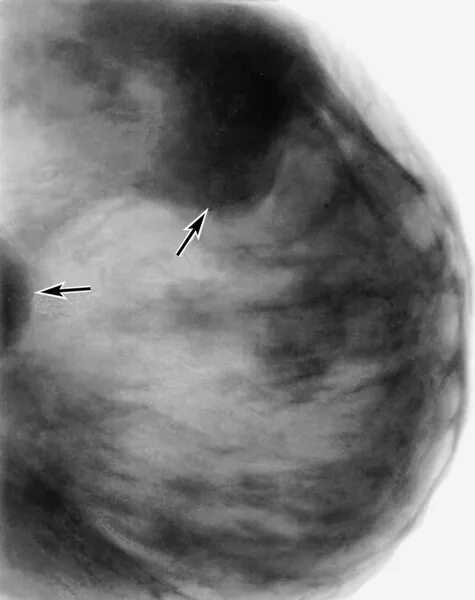

Диффузные доброкачественные